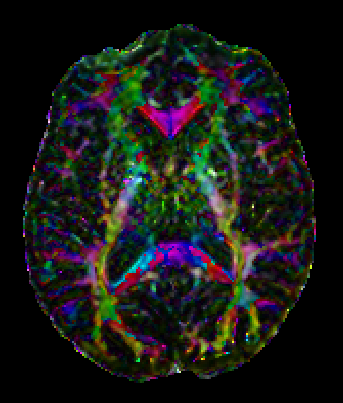

Colormaps What are they and what's the utility?

Colormap is, as the name suggest, a map between a variable and a color. In a 3D spatial context, the color is used to indicate a specific spatial direction, that is, a 3D spatial vector direction will be translated in a specific color. To find a correlation that bring value to the desired spatial visualization is a challenging task to designers and final users, because different choices may enhance different aspects. Below we propose a series of visual representations of different colormaps, each one is rendered in a sphere where the normal vector of a point in the surface represent the spatial direction considered on the map.

Absolute value Colormap

In this colormap the absolute value of the three component of the 3D Spatial vector (x,y,z) is translated into RGB colors. It is the most one used. Its color variation in orientation is smooth, but there is a serious problem with ambiguity in spatial orientation, that is, more than one direction is mapped onto the same color.